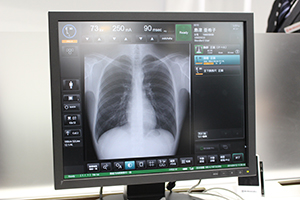

検査室内でのオペレーションも可能な |

撮影設定から画像表示までを1台のコンソールで可能 |

ブース中央では,3月に正式リリースとなった一般撮影システム「RADspeed Pro V4 package」を展示した。一般撮影検査は,胸部や腹部,整形外科など対象領域が広く,さまざまな撮影手技があり,また検査件数も多いことから,スループットの良さが求められる。RADspeed Pro V4 packageは,FPDの搭載や,1台で撮影設定から画像処理までを行えるタッチパネル式の統合型コンソールにより,より高いスループットをめざして開発されたシステムで,RADspeed Proシリーズの最上位機種としてラインナップに加えられた。コンソール1台ですべての操作,画像確認が可能であるが,X線管球操作部のモニタや,検査室内の壁面やスタンドに設置できる情報表示モニタ(オプション)でも撮影準備や画像確認,撮影プロトコールの変更ができるため,操作者の動線を短縮し,スループット向上に貢献する。さらに,オプションで小型のコンソールも設置できる。

搭載されるFPDは,立位撮影は17インチ×17インチの固定型パネル,臥位撮影は14インチ×17インチのワイヤレスパネルを基本としているが,シンチレータ(CsI,GoS)や固定/ワイヤレスなど,ユーザーの要望に応じた組み合わせで提供できる。長尺撮影など,臨床的有用性の高いアプリケーションも搭載可能となっており,グリッドは着脱可能で,小児撮影の際など外して撮影することで,線量を抑えた検査を行える。